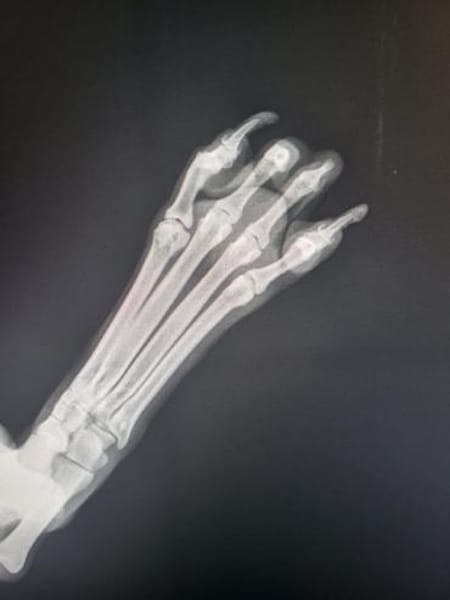

Ariel ist ein ca. 60 cm großer Rüde. Sehr verschmust und verkuschelt. Er hat hinten rechts ein leichtes Handicap. 1-2 Zehen fehlen. Wir gehen davon aus, dass er in eine Falle gekommen ist. Das Handicap zeigt sich, dass er leicht humpelt.